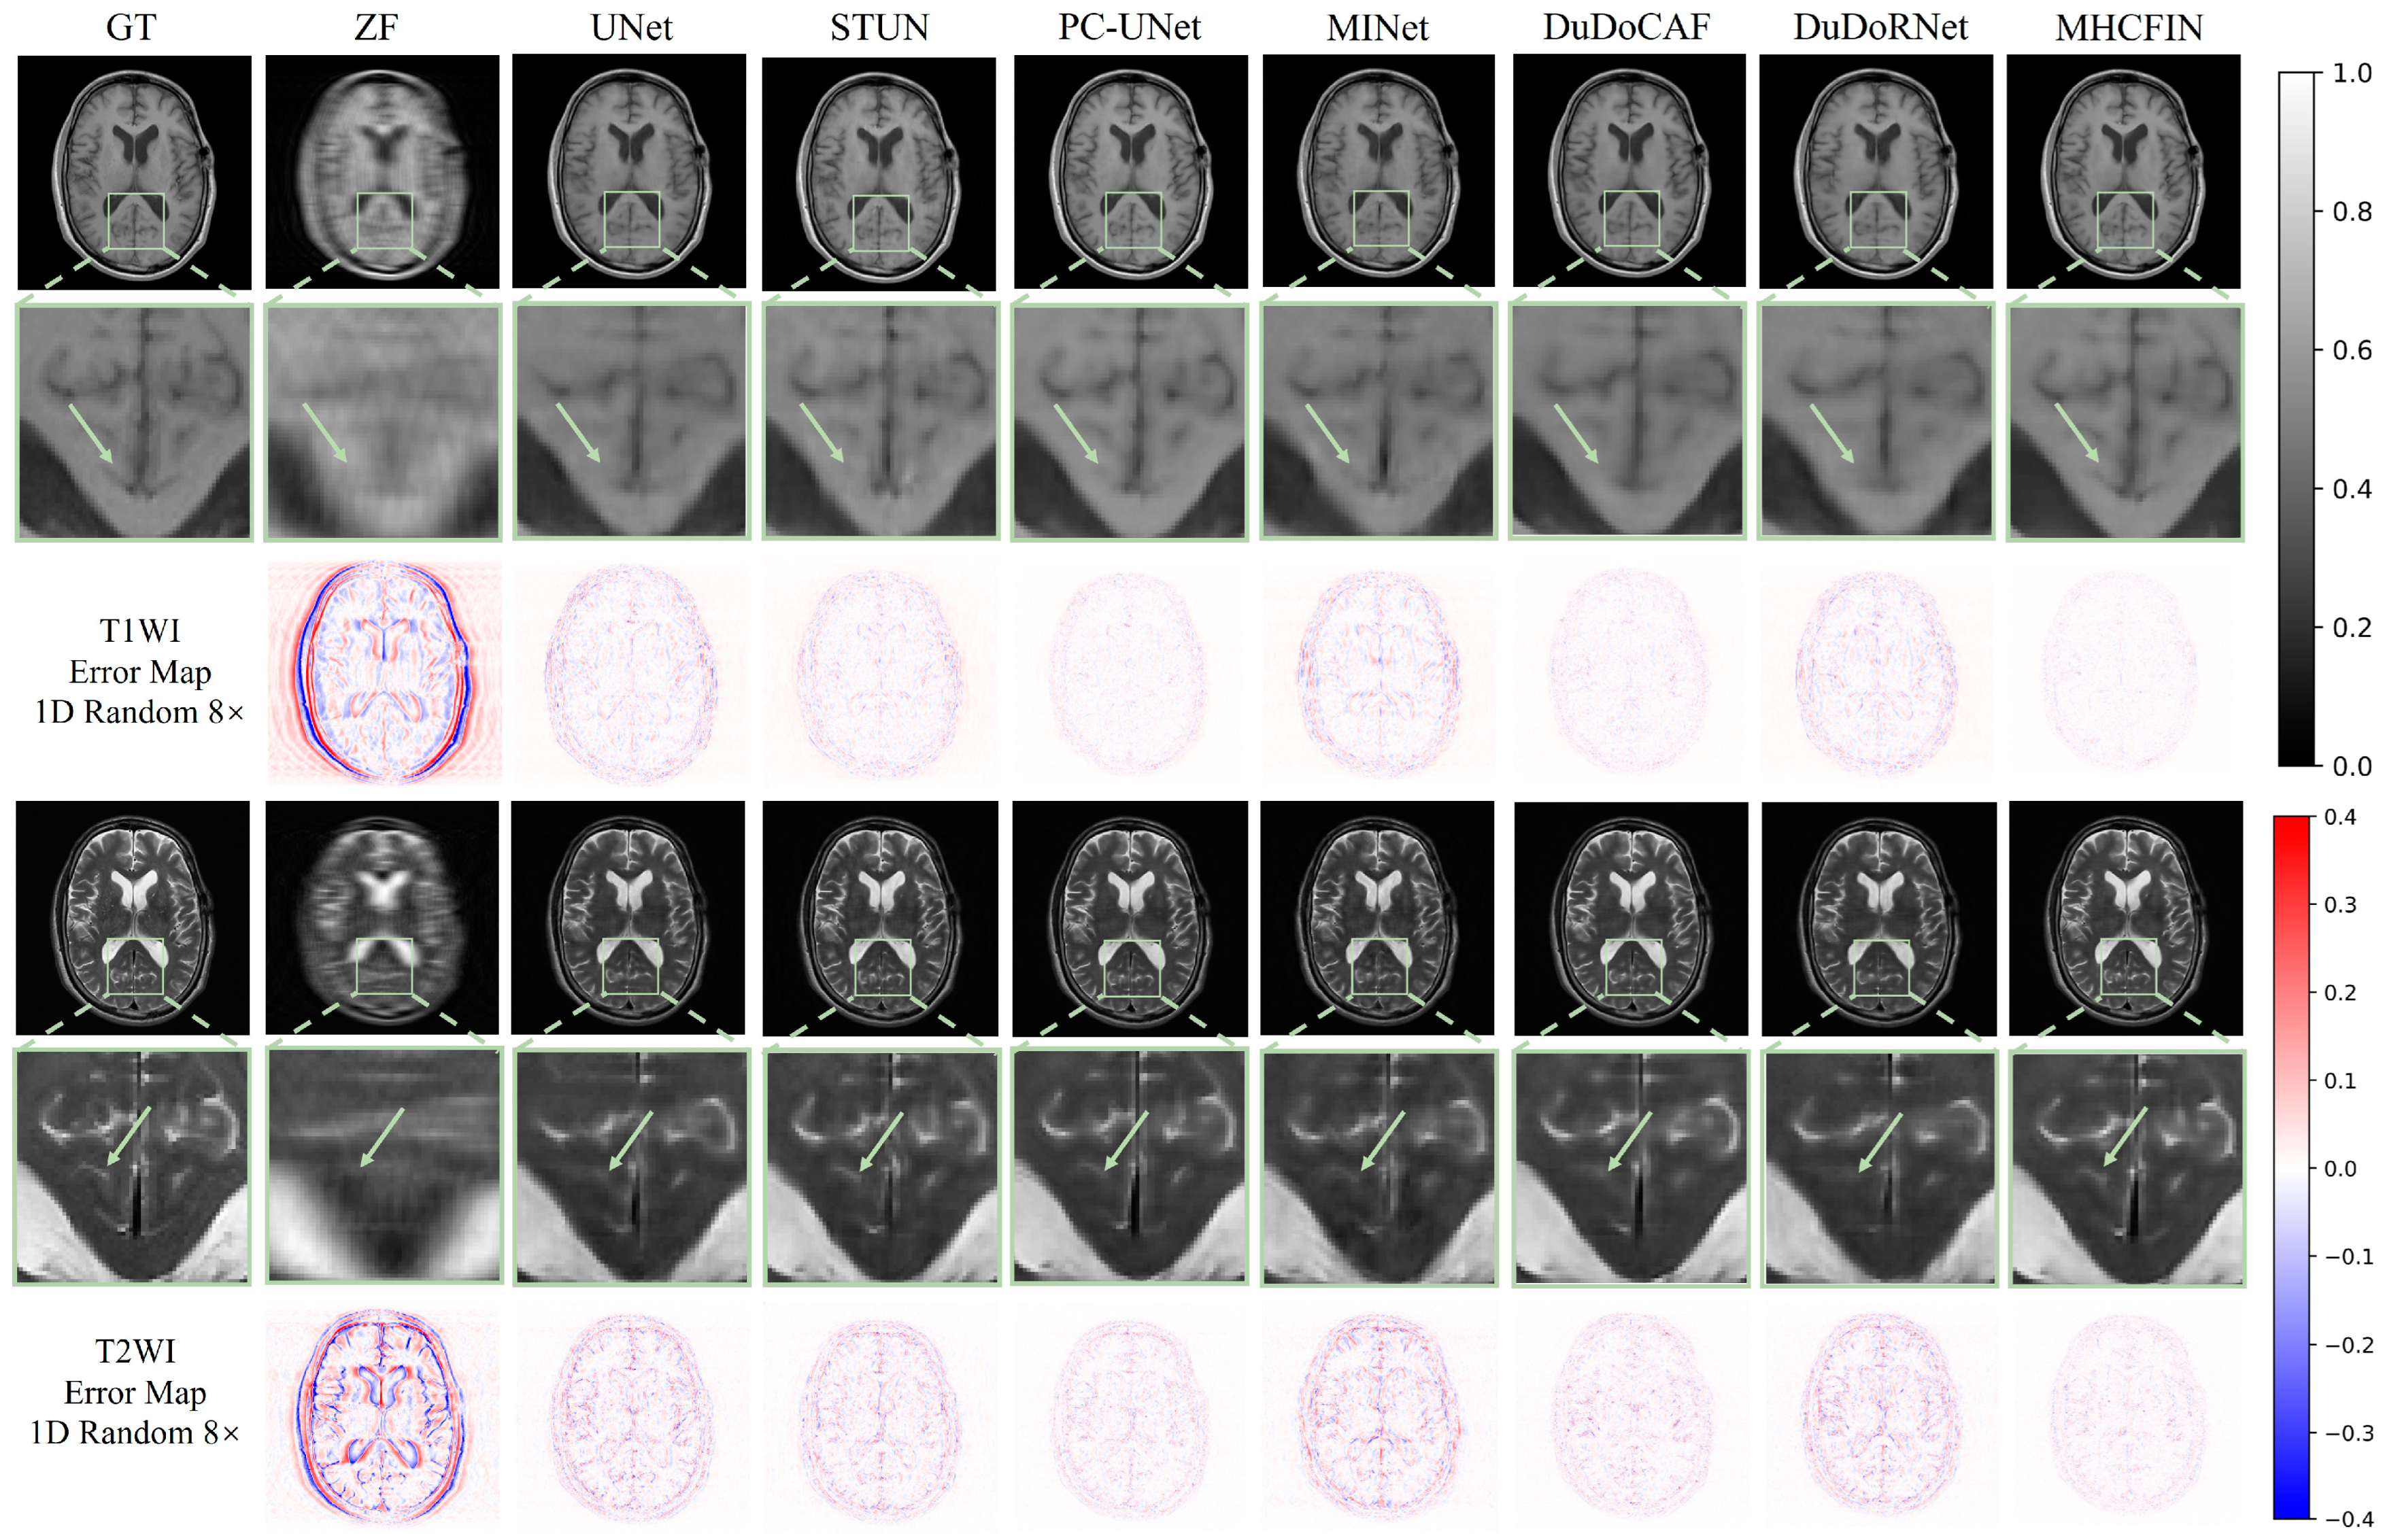

5.2. Qualitative Results